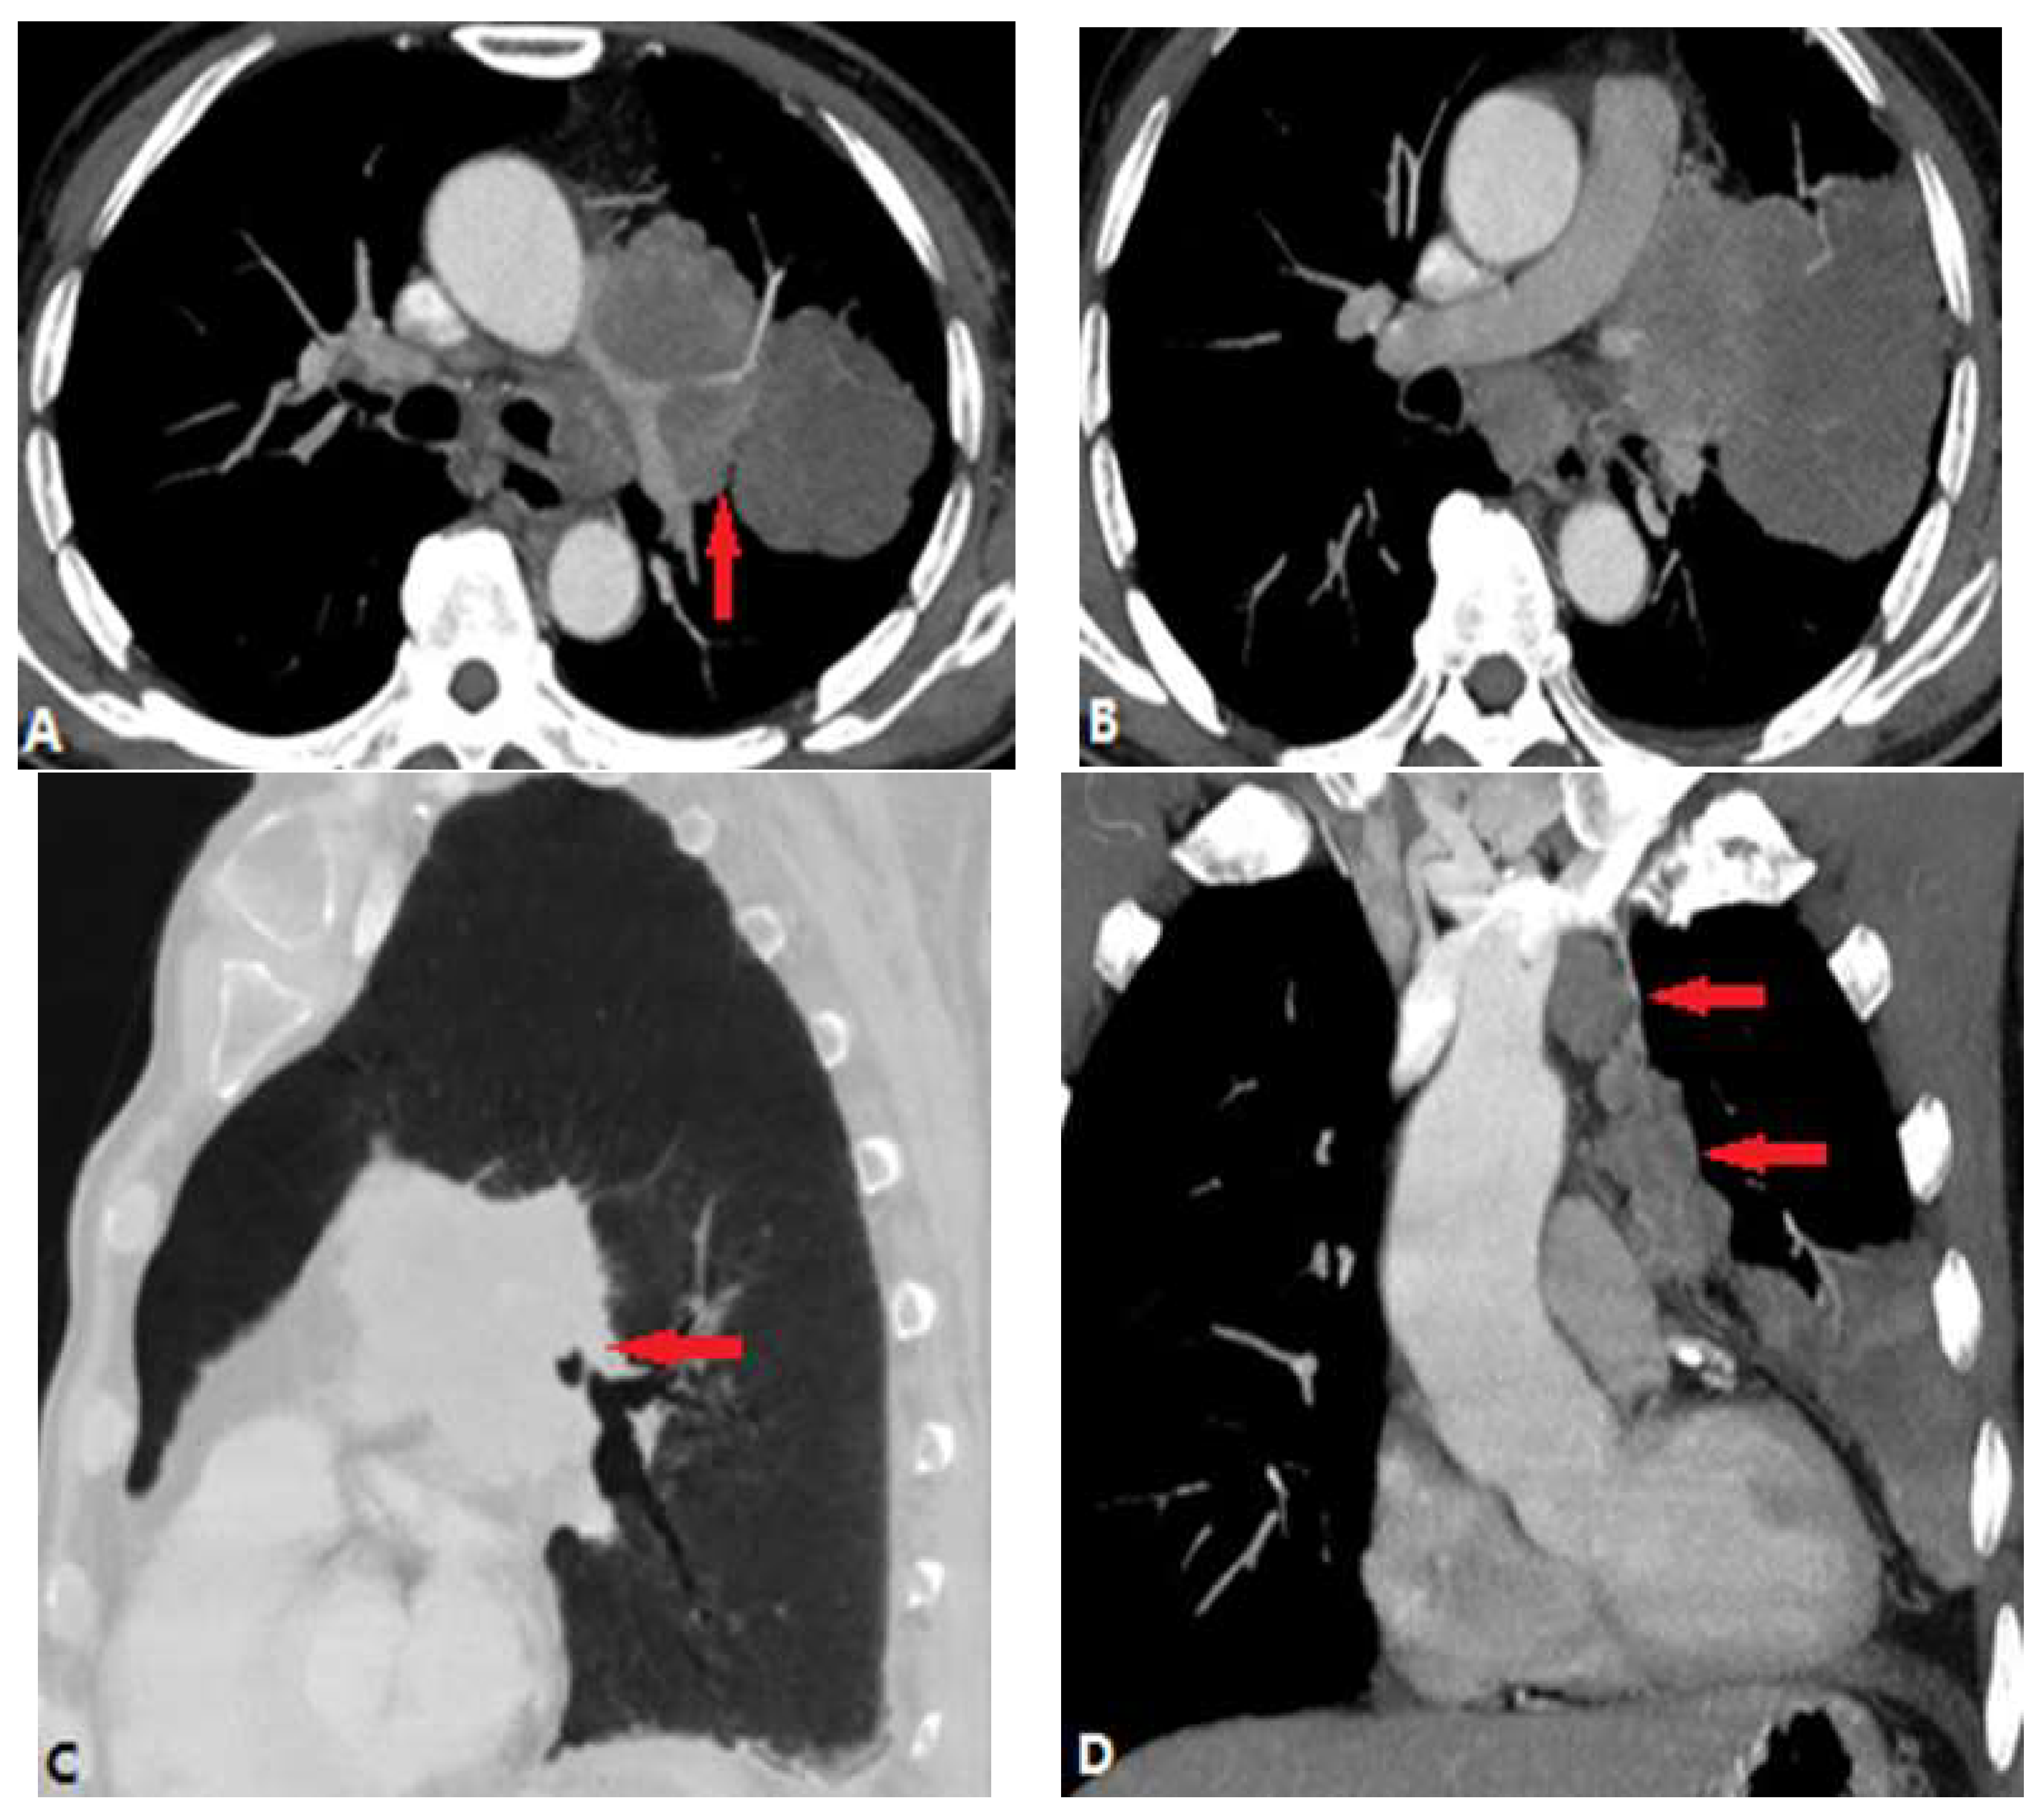

3.1.1. Pulmonary Thromboembolism (PTE)

3.1.2. In Situ Pulmonary Artery Thrombosis (PAT)

3.1.3. Pulmonary Tumor Embolism and Pulmonary Tumor Thrombotic Microangiography (PTTM)

3.1.4. Septic Pulmonary Embolism (SPE)